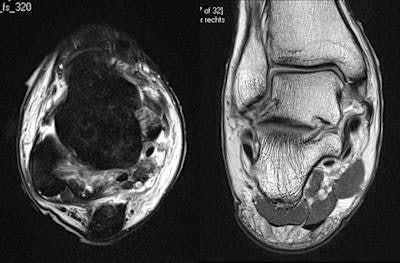

"There is a great debate about when best to image soft-tissue injuries. The athlete wants it immediately or at least within 24 hours. In my experience, it's better to wait between 24 and 48 hours because otherwise there's a high risk of having a false negative," stated Healy, who helps look after players from several Premiership and Championship football clubs, as well as Premiership rugby union teams, and has been involved in a Champions League thigh-muscle injury study since 2007. "If the imaging does not correlate with the clinical findings, then it's very important to repeat the imaging. Often, if you image too early, then you'll miss the extent of what's going on."

He has a simple rule about which modality to use: If the patient points to the abnormality with one finger, start with an ultrasound, but if the patient points to it with a hand, go straight to MRI. Also, ultrasound is better for imaging superficial structures, while MRI is better for deep structures.

Even if the clinical diagnosis is obvious, imaging is still required to gauge the extent of injury and identify any complications. If a significant injury has occurred and there are questions about patient management, then imaging is indicated for preoperative localization. Furthermore, if treatment has failed, imaging is needed to ensure the initial diagnosis was correct, Healy said. Finally, imaging can help document the existence, progression, or resolution of a disease, which can be useful for medicolegal reasons.